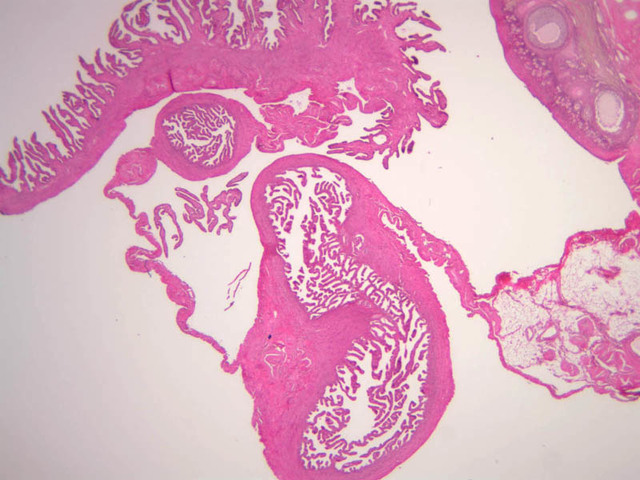

After ovulation, the oocyte passes into the uterine tube (i.e. oviduct, i.e. fallopian tube). Fertilization takes place here. This tube is subdivided into four regions:

The wall of the uterine tube consists of three layers; a mucosa, a muscularis, and an adventitial/serous coat (B-96 [2.5x, 10x-labeled, 20x, 40x] [2.5x, 10x, 20x, 40x]; B-97, monkey uterus [2.5x, 10x, 20x, 40x]). The mucosa is organized into folds that vary in their degree of complexity with the tube regions. The mucosa is lined by a simple columnar epithelium consisting of two cell types, ciliated and non-ciliated, secretory (B-93 [10x, 20x, 40x-labeled]). The mucosal lamina propria consists of somewhat loose connective tissue and is highly vascular. No muscularis mucosae are present. The muscularis consists of two layers of smooth muscle, the inner being oriented in a circular fashion and the outer longitudinally.

The structure of the uterine tube is under the control of, and responds to, cyclic changes in the levels of steroid hormones. Structural alterations to provide favorable transport for the oocyte commence anew with the beginning of each cycle and peak at mid-cycle just before ovulation. These include increases in height and number of the ciliated cells as well as active secretion in the secretory cell. For the remainder of the cycle thereafter, dedifferentiation occurs. The cyclic changes occur to a greater extent in the upper ampulla and infundibulum. The margin of the infundibulum is drawn out into numerous finger-like processes called fimbrae. Microscopic examination of these will reveal that within the lamina propria are numerous large blood vessels, especially veins, as well as bundles of smooth muscle forming an intervening network. At the time of ovulation, the vessels become enlarged with blood, causing turgidity, which when combined with smooth muscle contraction brings the infundibular opening into close apposition with the ovarian surface.